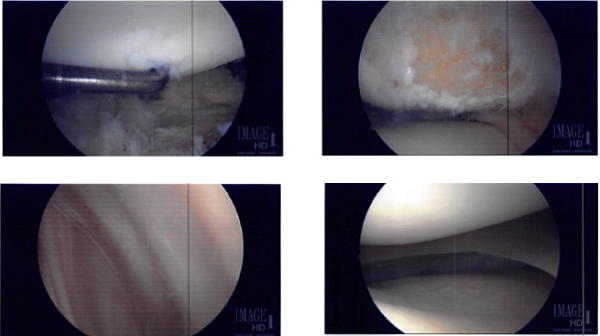

The tourniquet was inflated. Lateral entry portal was made and the scope was entered. Osteochondral OA grade 3 to grade 4 damage was found on the lateral inferior patella. Lot of debris was found in the knee as in the suprapatellar pouch and medial gutter.

The knee scope was moved to the medial compartment where a lot of debris as well as medial meniscus tear could be seen. medial entry portal was made. A probe was entered and meniscal tear were examined and pictures! was taken.

A shaver was inserted to clean off the debris as well as margins on the medial meniscus. The final balancing of the medial meniscus was performed. The lesion was also debrided. Microfracture of patellar osteochondral defect was done using pigtail punches and subchondral fat globules could be seen from the microfracture site.

Intraoperative Images from start to final process